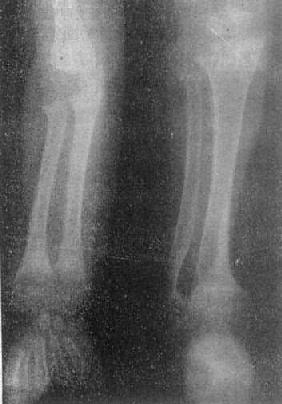

图2-1-8 前臂小腿骨骨质软化—佝偻病骨质普遍密度减低,骨皮质薄,边缘不清,骨小梁

模糊,骨变弯、变形。干骺端宽大呈杯口状变形,骺与干骺干骺端距离增宽。骺边缘模糊。腕骨出现少

骨质软化的X线表现主要是由于骨内钙盐减少而引起的骨密度减低,以腰椎骨盆为明显。与骨质疏松不同的是骨小梁和骨皮质边缘模糊,系因骨组织内含有大量未经钙化的骨样组织所致(图2-1-8)。由于骨质软化,承重骨骼常发生各种变形(图2-1-9)。此外,还可见假骨折线,表现为宽约1~2mm的光滑透明线,与骨皮质垂直,边缘稍致密,好发于耻骨支肱骨股骨上段和胫骨等。